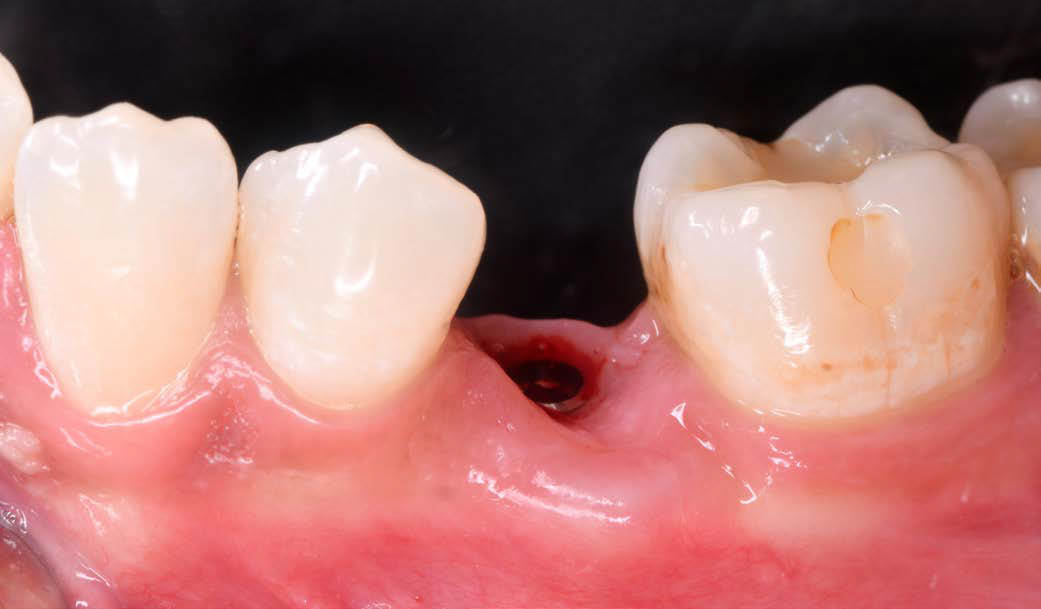

Figure 3: Condition after extraction and preservation of the buccal root portion |

A 26-year-old female patient was referred to my practice. Tooth 35 was deemed non-restorable. A CBCT scan showed the buccal bone plate was missing. Especially in aesthetic zones, we aim to reduce tissue collapse post-extraction (up to 50%). We considered various ridge preservation techniques to minimize this risk.

I chose the Socket Shield Technique, a minimally invasive method to reduce tissue shrinkage and achieve better long-term aesthetic outcomes. The technique requires healthy periodontal tissue and an intact root, both of which were present. The tooth is partially extracted, leaving the buccal root portion to support the soft tissue. This maintains the buccal periodontal attachment, allowing the tissue to behave as if the tooth were still in place. Hürzeler et al. introduced this technique in 2010 to reduce tissue shrinkage during immediate implantation.